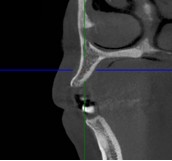

(术前CT)CT检查显示尖牙区牙齿缺失

3. CBCT显示:水平骨量不足3.5mm。